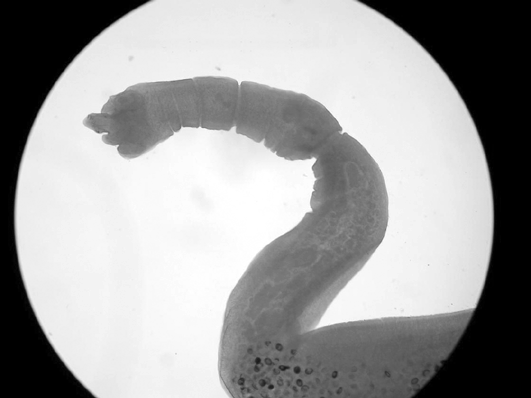

- Echinococcus granulosus, cuc de la hiatidosi, que és un endoparàsit del tub digestiu del vertebrats, entre ells l'home.

Els col·lectius de risc són els treballadors que per la seva activitat laboral mantenen un contacte estret amb gossos, a les zones rurals o a les urbanes. Un exemple del primer grup són els pastors i les seves famílies, especialment els que viuen a zones endèmiques. Exemples del segon grup són els veterinaris, ensinistradors de gossos i treballadors d’escorxadors.

Les mesures de prevenció són el control estricte del sacrifici d’animals infectats, la posterior incineració i/o soterrament a gran profunditat, per evitar d’aquesta manera l’accés dels gossos a vísceres infectades dels hostes intermediaris (herbívors) i així evitar el contagi als humans.